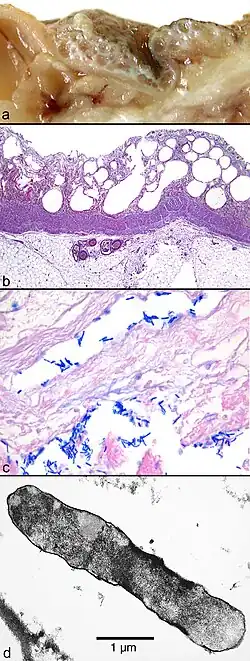

(a) Macroscopic picture of the edematous intestinal wall with multiple submucosal and subserosal cysts

(b) Histological picture of the intestinal mucosa with nonreactive necrosis

(c) Gram stain of cysts with large, rod-shaped bacteria

(d) Electron microscopic picture of a bacterium found in a submucosal cyst